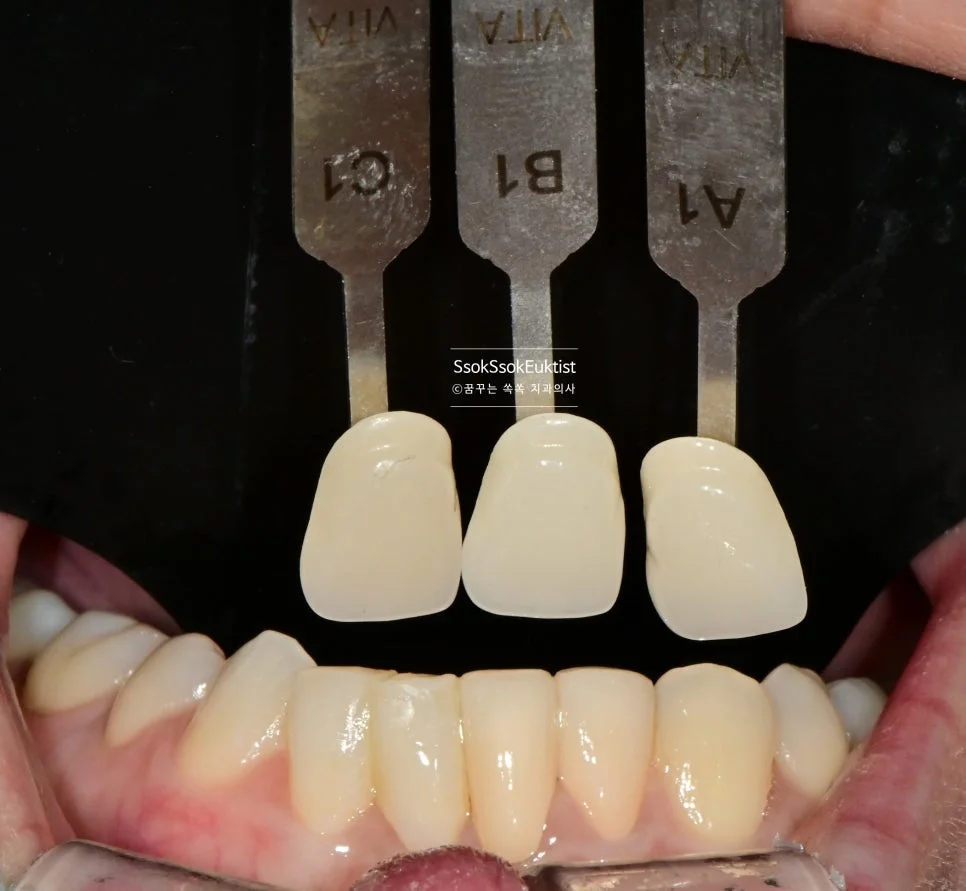

가장 어울리는 색상을 찾기 위해 Shade-guide를 적용하여 최대한 많은 정보를 기공실에 전달합니다^^ 그렇게 하여 아래 앞니 4개의 크라운을 제작해 보았습니다.